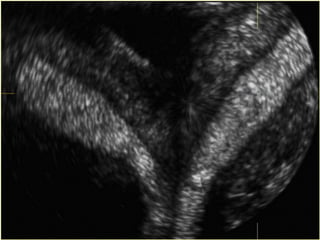

Congenital Uterine Anomaly n Diagnosis: History Pelvic exam Hysterosalpingography U/S MRI Laproscopy Hysteroscopy IVP or U/S (Exclude Renal anomaly )

Congenital Uterine Anomaly n Treatment: 1- Double uterus (didelphic uterus): no need to treat. 2- Bicornate ut. --------- Strassmann procedure ( if indicated ) 3- Ut. Septum --------- (BCP for dysmenorrhea ), Tompkins metroplasty or Hysteroscopic resection of septum ) 4- Unicornate ut. -------- Surgery indicated if there is blind horn which cause symptom----- surgical resection of blind horn.